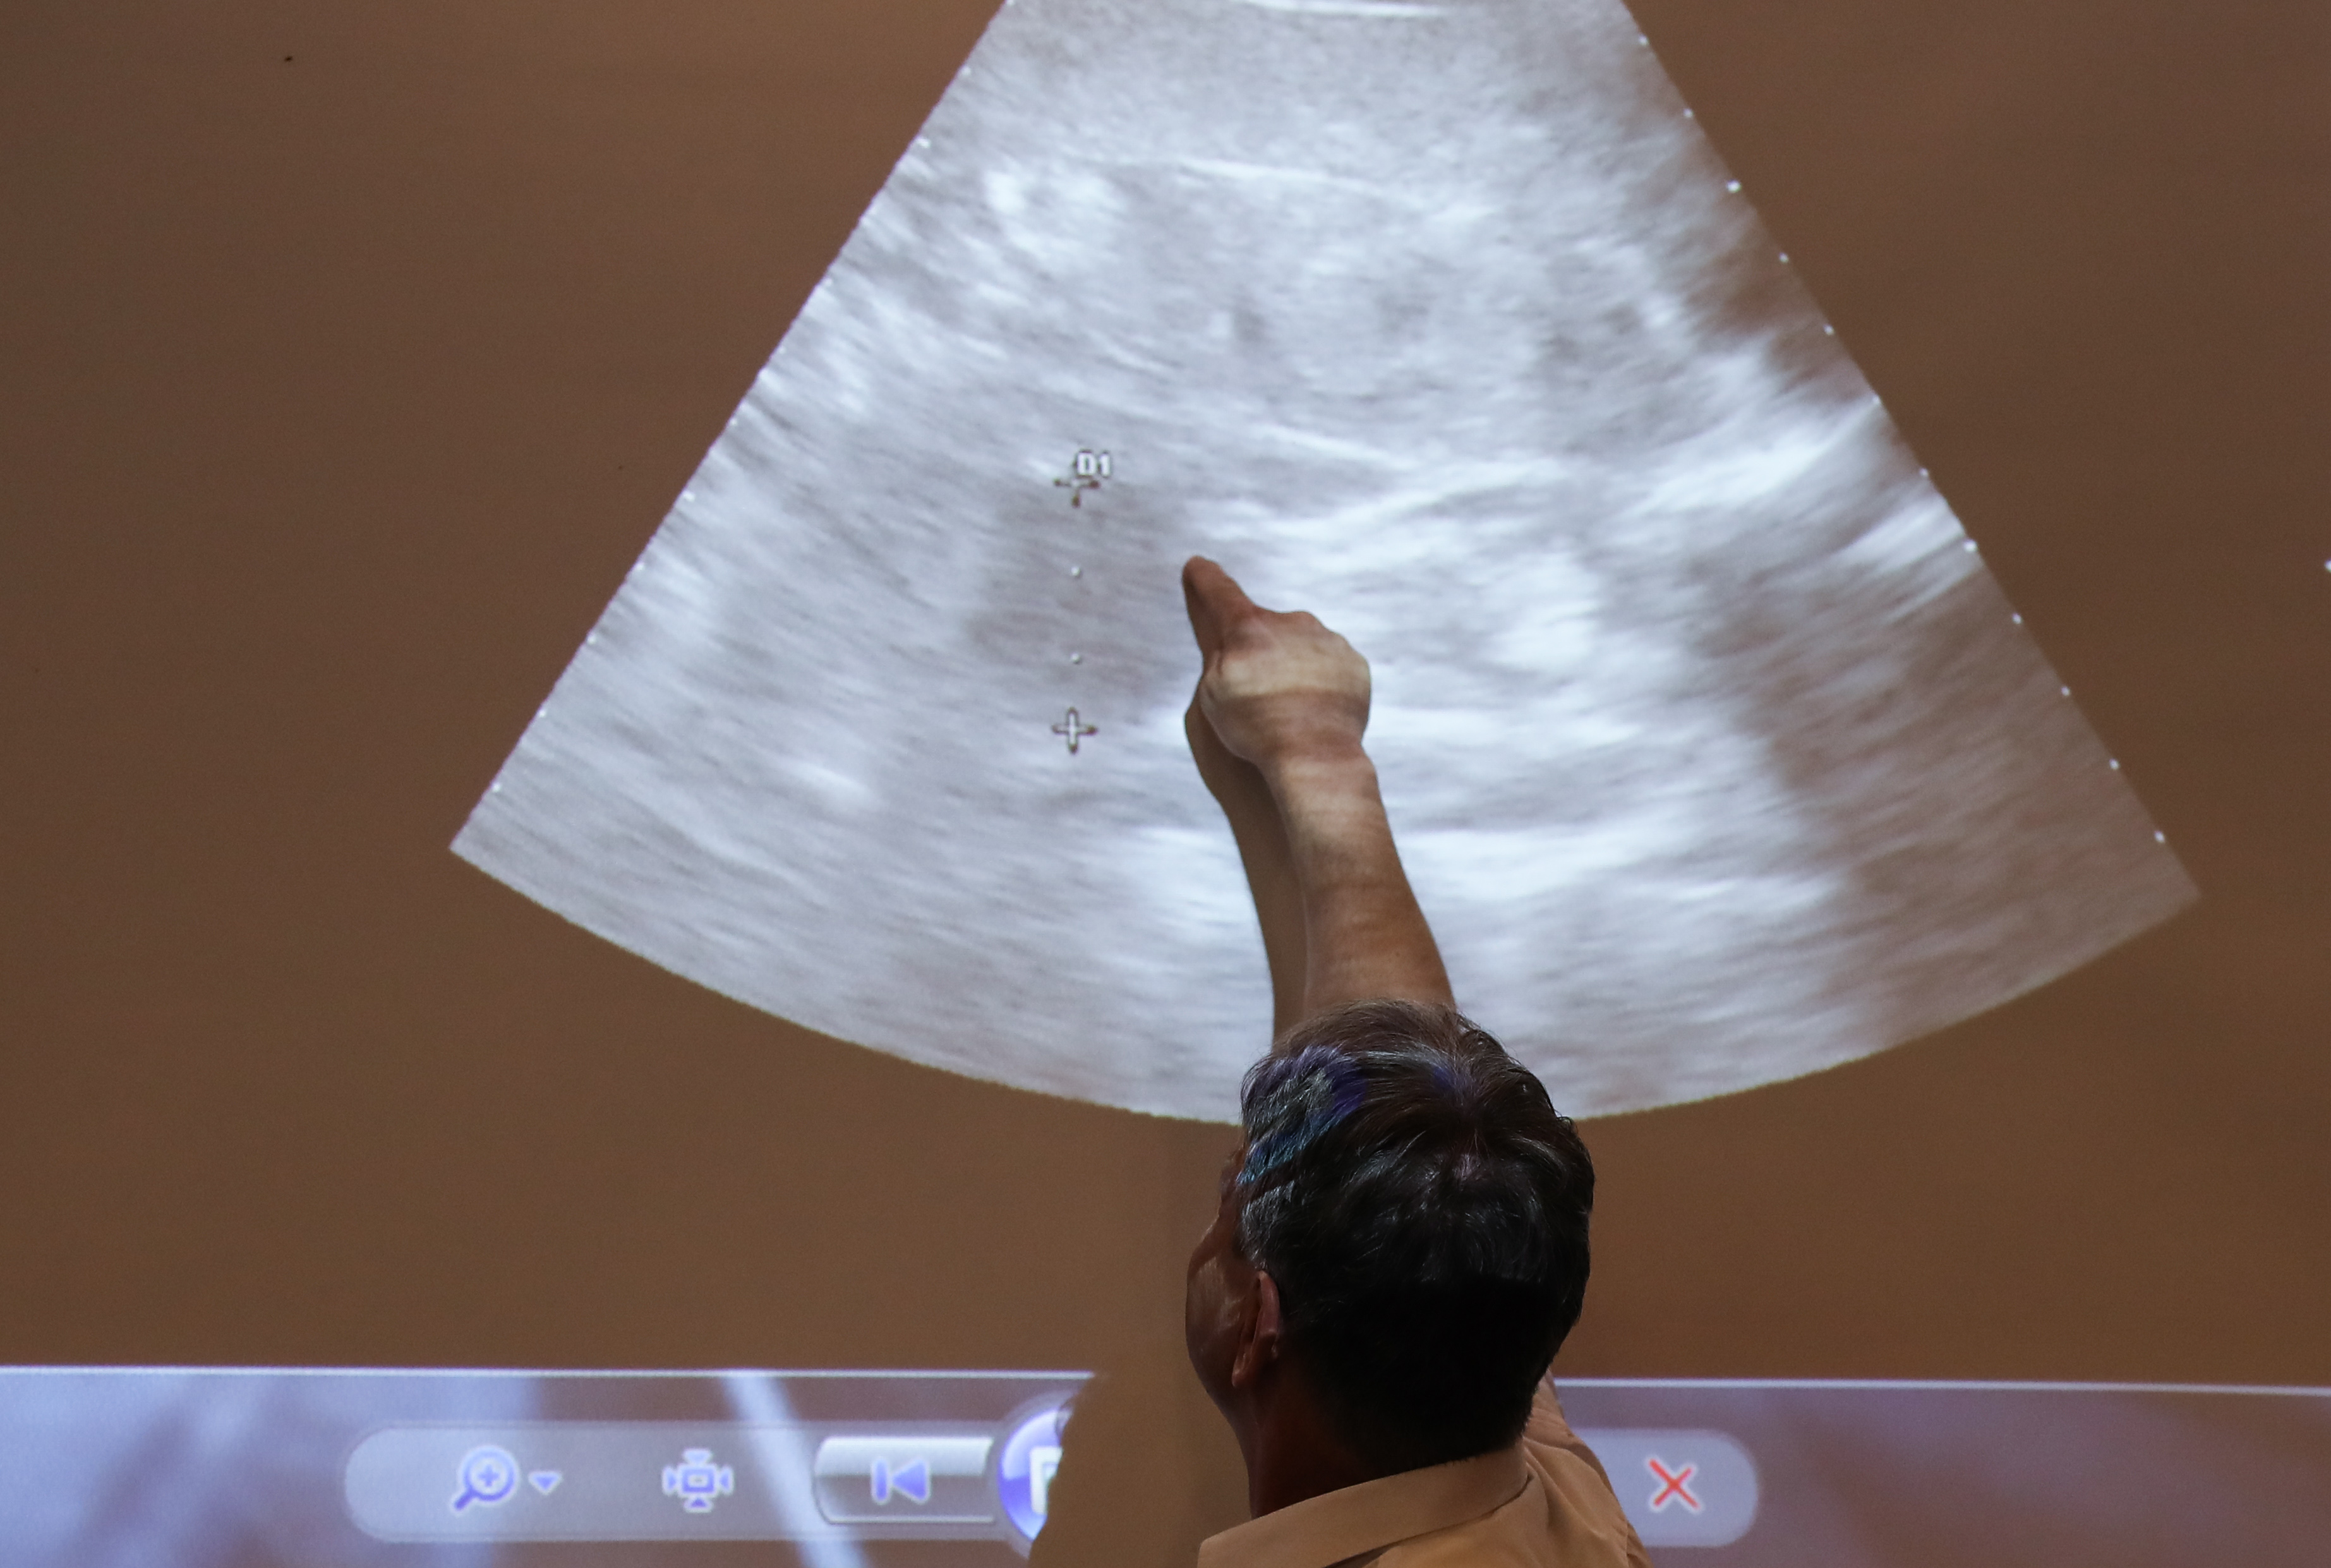

Thomas Hildebrandt, head of the reproduction management department at Germany's Leibniz Institute for Zoo and Wildlife Research, points the position of the embryo during a press conference at the Zoo Berlin in Berlin, capital of Germany, on Aug. 14, 2019.(Xinhua/Shan Yuqi)

Meng Meng's altered behavior hinted a pregnancy, and ultrasound images and hormone tests have also provided extra reasons to expect a panda cub in a few weeks' time, said Zoo Berlin, known as Germany's oldest zoological garden, home to almost 20,200 animals of around 1,380 species.

Germany's Leibniz Institute for Zoo and Wildlife Research (IZW) is conducting regular examinations on Meng Meng. Thomas Hildebrandt, head of the reproduction management department at IZW, said the most recent test on Wednesday showed that Meng Meng's ovaries are activated, her uterus becomes much larger, and a small bulge is visible that could be one or two embryos.

"Although phantom pregnancies are relatively common in giant pandas, at the moment we are around 85 percent sure that Meng Meng is actually expecting," said Hildebrandt.

Andreas Knieriem, director of Zoo Berlin, told Xinhua that only when they see a pumping heart of fetus can they be more sure. "Never in the history of Berlin that such stage of a pregnancy of giant pandas is achieved, so we are very hopeful," he added.